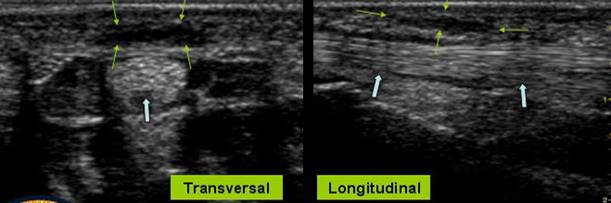

COMPRESIUNEA NERVULUI MEDIAN

Parestezia primelor 3 degete

Hipertrofia n.median → cu hiperemie pe Doppler

Aspectul nervului pe IRM este normal